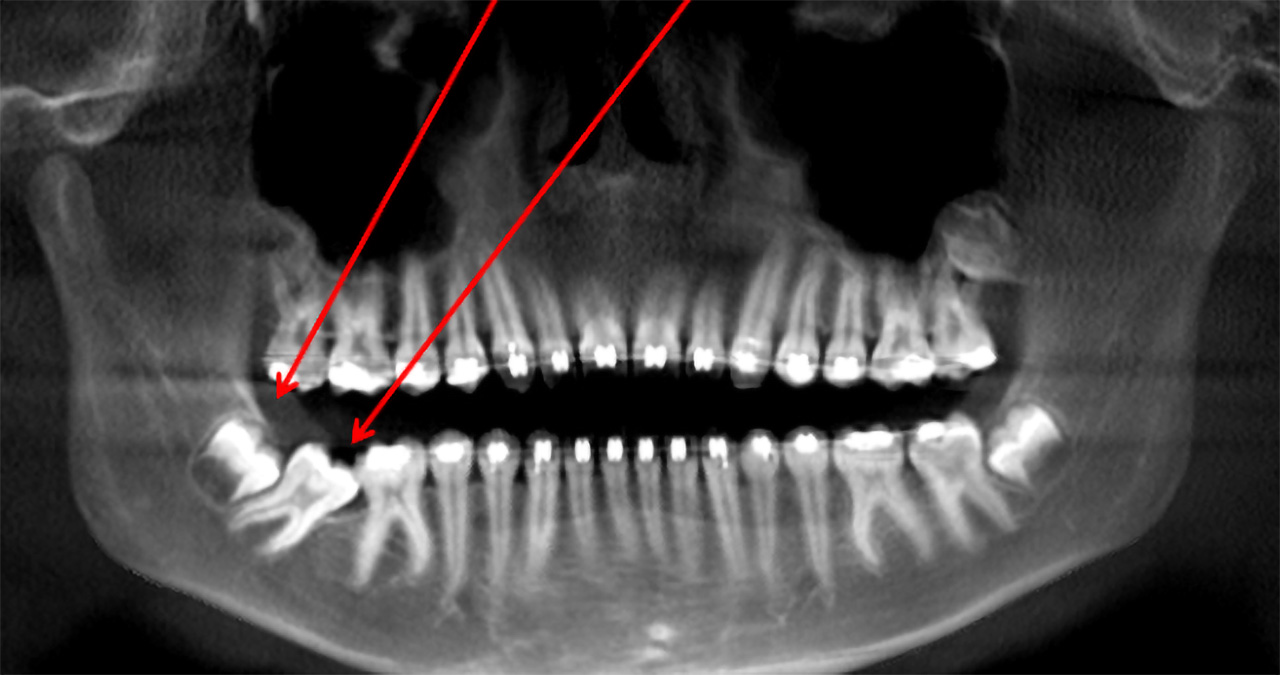

Panoramic X‑ray of a 14‑year‑old patient with an impacted wisdom tooth blocking the lower second molar from erupting into its normal position.

Figure 1. Panoramic X‑ray of a 14‑year‑old patient with an impacted wisdom tooth blocking the lower second molar from erupting into its normal position.

Dr. John Wessel, oral and maxillofacial surgeon at our office in Rock Hill, SC, recently had a 14-year-old patient referred by his orthodontist for impacted wisdom teeth with a lower second molar that had erupted into the wrong position.

Instead of standing upright as expected, the lower second molar was angled forward about 45 degrees and locked against the first molar. The wisdom tooth behind it was blocking the path the second molar needed in order to surface correctly in the dental arch.